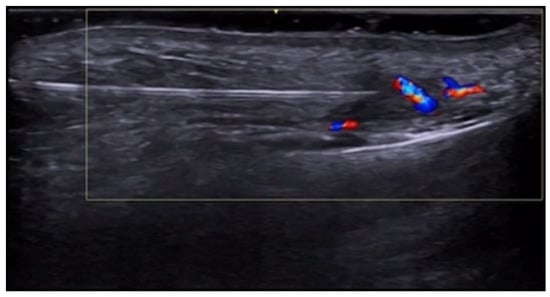

- Di Battista, M.; Vitali, S.; Barsotti, S.; Granieri, G.; Aringhieri, G.; Morganti, R.; Dini, V.; Della Rossa, A.; Romanelli, M.; Neri, E.; et al. Ultra-high frequency ultrasound for digital arteries: Improving the characterization of vasculopathy in systemic sclerosis. Semin. Arthritis Rheum. 2022, 57, 152105. [Google Scholar] [CrossRef] [PubMed]